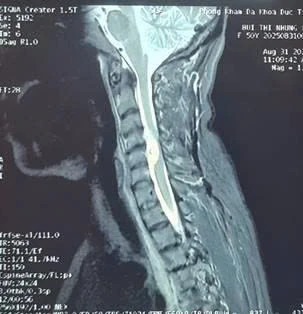

Hình ảnh khối u tủy cổ trên phim chụp Cộng hưởng từ.

Bệnh nhân nhập viện trong tình trạng tay chân yếu, đi lại khó khăn, tay phải liên tục bị đau và co giật do khối u chèn ép mạnh vào tủy sống. Kết quả chụp Cộng hưởng từ cho thấy khối u nằm ở mặt trước tủy sống cổ C4/5, chiếm tới 2/3 diện tích ống sống, gây chèn ép nặng nề và nguy cơ liệt tứ chi nếu không được can thiệp kịp thời.